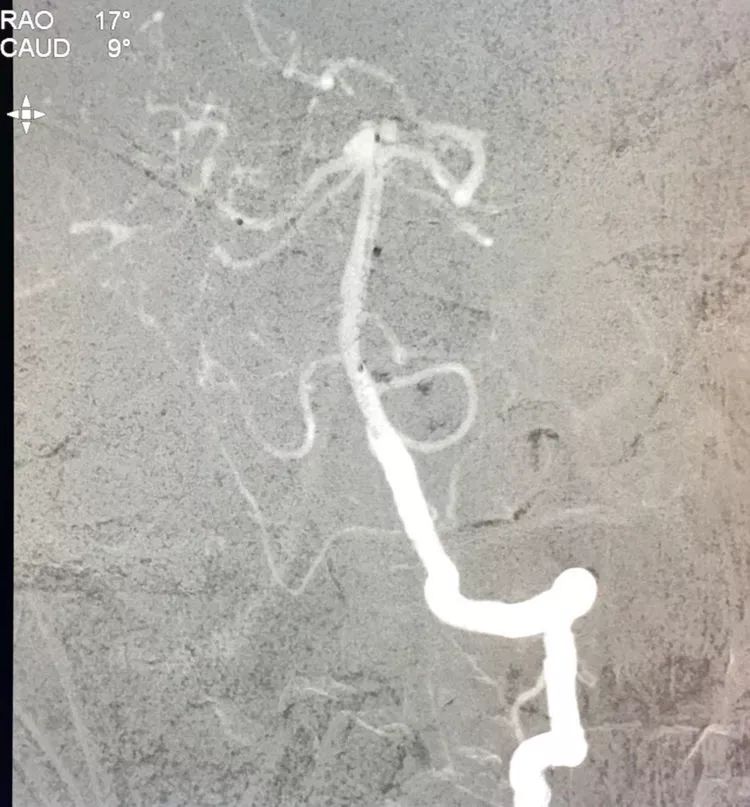

将LVIS支架(3.5×15)跨瘤颈释放于右侧PCA-基底动脉内

在支架保护下输送弹簧圈栓塞瘤腔

此时从工作位(右斜17°反汤9°)看弹簧圈分布致密,微导管头已被顶到瘤颈处

工作位造影看动脉瘤栓塞满意,子瘤已不显影,是不是可以收手了呢?